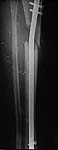

S/P Nailing

AP

lateral